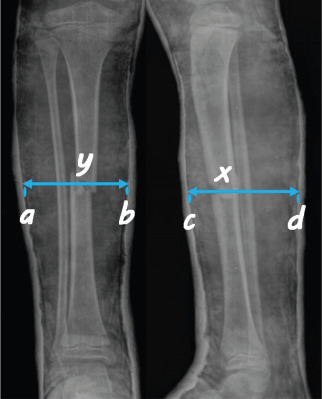

Methods: The patients aged 0-16 years who were admitted to the emergency department between January 2014 and January 2018, with tibia diaphysis or distal third fractures and treated with CRC were included the study. A total of 196 pediatric patients (41 females, 155 males) were retrospectively evaluated. The radiographs on admission were analyzed in terms of fracture type, location of the fracture, presence/location of the fibula fracture as well as initial angulation in both planes, translation, and the time of definitive cast. On radiographs taken after closed reduction and final casting, angulation in the coronal and sagittal planes, amount of translation (%), CI, GI, and TPI were measured. Logistic regression analysis was used to evaluate the risk factors of re-displacement.